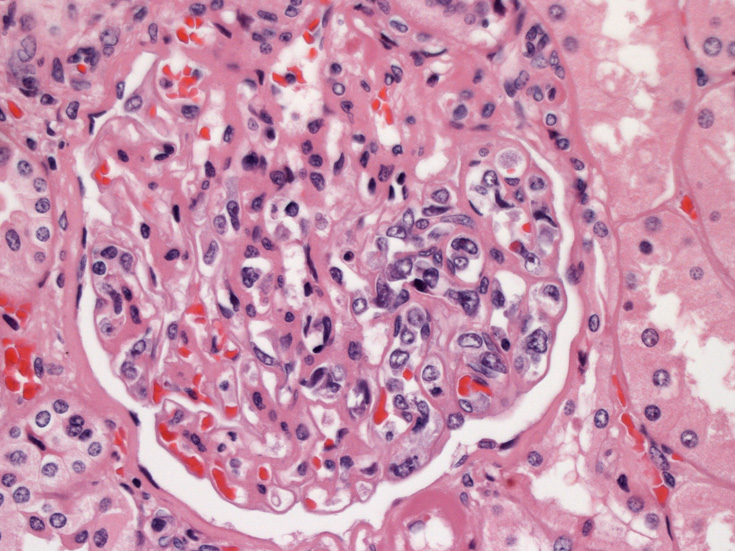

腎臓;糸球体係蹄内に腫瘍細胞が増殖するほか細腎動脈にもみとめられる。

生検組織により血管内腔を塞ぐように大型異型リンパ球が増殖していることを確認することが診断の要件である。血管内増殖の病変分布が本病型では, 脳, 肺, 肝, 腎, 副腎, 皮膚, 骨髄など特有である。しかし大細胞型B細胞リンパ腫にはこのような臓器を選択的に侵襲するが, 血管内腔には増殖しないものがあることに留意が必要である。